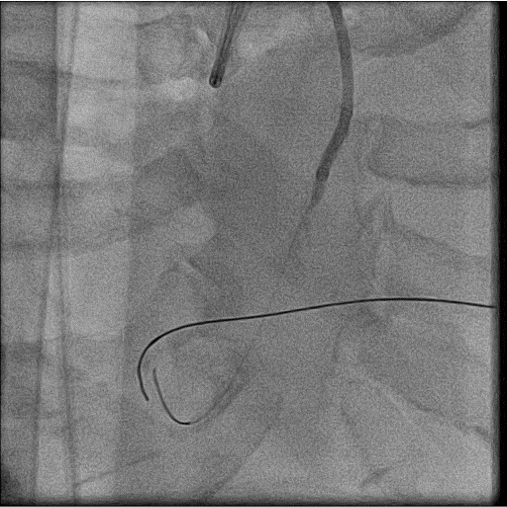

The coronary angiogram showed middle LAD CTO, LCX critical stenosis and RCA CTO with collateral from LCX. J-CTO score for LAD was 3 points . J-CTO score for RCA was 4 points. The CHIP PCI score was 11.

The procedure was done in two stage. For first stage, we use upfront IABP as a mechanical support with ECMO access route prepared and ECMO team standby. The LAD CTO was the first target as it was relatively short, not a donor vessels and would provide greatest benefit to the patient. With antegrade approach and wire escalation technique ( Fielder XTA, Fielder XTR, Gaia 1st), we finally punctured into the proximal cap with Gaia 3rd and immediately deescalate the wire to Sion black to navigate through the CTO body and finally managed to reach distal true lumen with a Sion Black. Then we did the circumflex lesion starting with a Sion Black. However, the Sion Black and Fielder XTR could not cross the lesion. We then escalate the wire to Gaia 1st.

For 2nd stage procedure, we did the RCA CTO with primary retrograde approach due to ambiguous proximal cap and distal cap is a bifurcation. The initial retrograde wire escalation technique was failed to puncture into the distal cap by using SIon, Gladius EX and even Gaia 3rd wire. So we shift to antegrade approach starting with Gladius EX wire but we failed too. Then retrograde puncture was reattempted with Miracle 6 wire. It successfully punctured into the distal cap. By using kissing wire technique, antegrade wire entered distal true lumen. The procedure was finished with balloon dilatation and stenting. We were abled to preserve the distal PL and PDA branch.